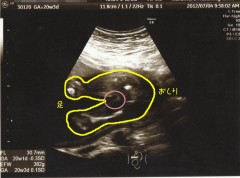

前回の検診で初の性別診断をしてもらいました!!

赤丸のところ…ついてなさそうですよね!?

ってことで今のところ女の子説が有力です(*´ェ`*)

隠れているだけという可能性もあるので、まだハッキリと断定はできません!